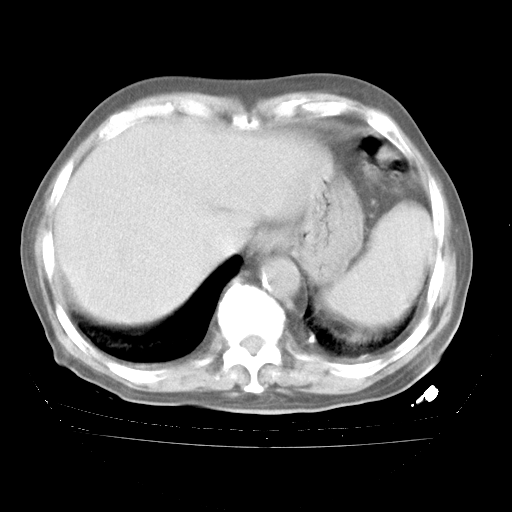

4月28日肺部CT——再次出现类似去年5月9日——磨玻璃样、间有“粟粒样”改变。

4月28日肺部CT